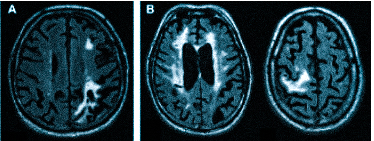

Множественные ишемические очаги при сосудистой деменции на МРТ: отсутствие памяти на недавние события и неадекватное поведение не являются признаками старости, своевременная диагностика деменции и патогенетическая терапия помогут замедлить прогрессирование болезни

МРТ — обследование, которое проводят не только при головной боли. Магнитно-резонансная томография поможет установить причины следующих жалоб:

ухудшение памяти, слабоумие (деменция);